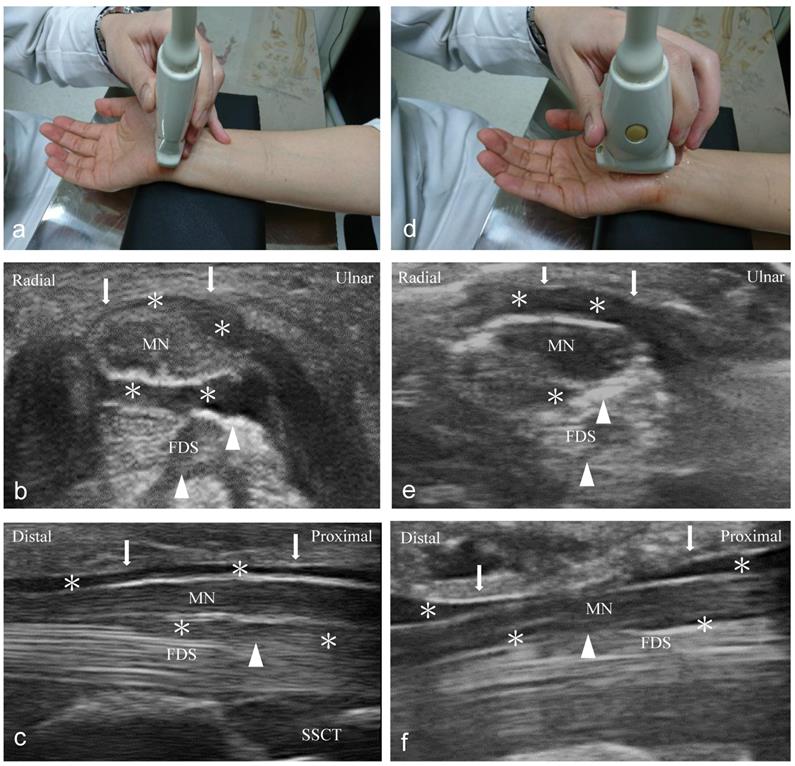

Ultrasound-guided short- and long-axis injection (Figure 1)

An independent physician with 7 years of experience performed ultrasound-guided injections with a 10-18-MHz liner-array transducer (MyLab™25Gold, Esaote, Genova, Italy) [6]. A 25-gauge, 2-inch needle was used, without the administration of a local anesthetic throughout the procedure. At the scaphoid-pisiform level, the MN was observed at the inlet of the carpal tunnel. In the short-axis group, we used 2 mL NS to hydrodissect the MN from the SSCT with an in-plane ulnar approach. A residual 3 mL NS was delivered to detach the MN from the FR (Figure 1a to c). In the long-axis group, a total of 5 mL NS was delivered into the intracarpal canal with an in-plane approach to detach the MN from the FR advancing from the wrist crease to the palm (Figure 1d to f).

Ultrasound-guided injection image (left: short-axis injection; right: long-axis injection). (a) The position of in-plane short-axis injection at proximal inlet of the carpal tunnel. (b) The short-axis view shows that the MN separated from the subsynovial connective tissue (arrowheads) via hydrodissection (HD) (*: Injectate). (c) The short-axis view shows that the MN was separated from the flexor retinaculum (FR) (arrows) via HD (*). (d) The position of the in-plane long-axis injection advancing from the wrist crease to the palm. (e) The long-axis view shows swollen nerve fascicles, FR (arrows), and inflamed tendons in the same plane. (f) The long-axis view shows that the MN separated from the FR (arrows) via HD. MN: median nerve; FDS: flexor digitorum superficialis; FDP: flexor digitorum profundus.

Other effectiveness, safety concerns should also be discussed. Previous research advocated that a short-axis scan is superior to a long-axis scan considering that the ultrasound image may be confused as swollen nerve fascicles, muscles, and inflamed tendons in the same plane of the long-axis scan; raising concerns of nerve trauma due to long-axis injection (Figure 1e) [42]. Furthermore, the short-axis approach benefits from faster learning with better accuracy of the injection because the operator has better flexible control of the needle from the initial penetration site to the MN which could contribute to injection precision as compared to the long-axis approach (Figure 1) [12, 15, 43]. Hence, it may offer a lower risk of nerve injury with a parallel needle approach to the oval-shaped MN that clearly visualizes the whole needle and neurovascular tissue. Nevertheless, the comparison of safety and the learning process between short- and long-axis HD was not performed in our study because all the injections were performed by an experienced physician. As both short- and long-axis HD were effective based on our results, the intervention choice would depend on the operator's preference. We advocate performing an in-plane short-axis intervention above and below the MN, especially for beginners, as this may have the advantage of being safer, easier to learn, and potentially more effective for HD compared to the long-axis approach. Recently, Lam et al. [44] advocated the long-axis approach to the MN from distal to proximal, and start the HD using out-of-plane technique first to release the nerve from the FR and SSCT. When the MN has been released from the soft tissues both above and below, the needle is put back to the top of the nerve and the transducer turns 90 degrees to become in-plane with the needle and the hydrodissecting to more proximal part of the nerve. Although Lam's method can comparatively separate a longer length of nerve via a single insertion point, the learning process is much longer. Further studies are also encouraged to compare the clinical efficacy of the long-axis approach in Lam et al's review and our study.